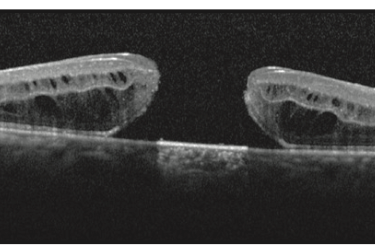

O diagnóstico para detecção do buraco de mácula é feito através de exames que ampliam essa região permitindo observar o grau de comprometimento são eles: mapeamento de retina, retinografia, angiografia de retina e tomografia de coerência óptica (OCT).

O exame mais importante nessa situação será o de OCT, que ira nos mostrar o tamanho do buraco e outros sinais de bom ou mal prognóstico de fechamento do buraco macular.